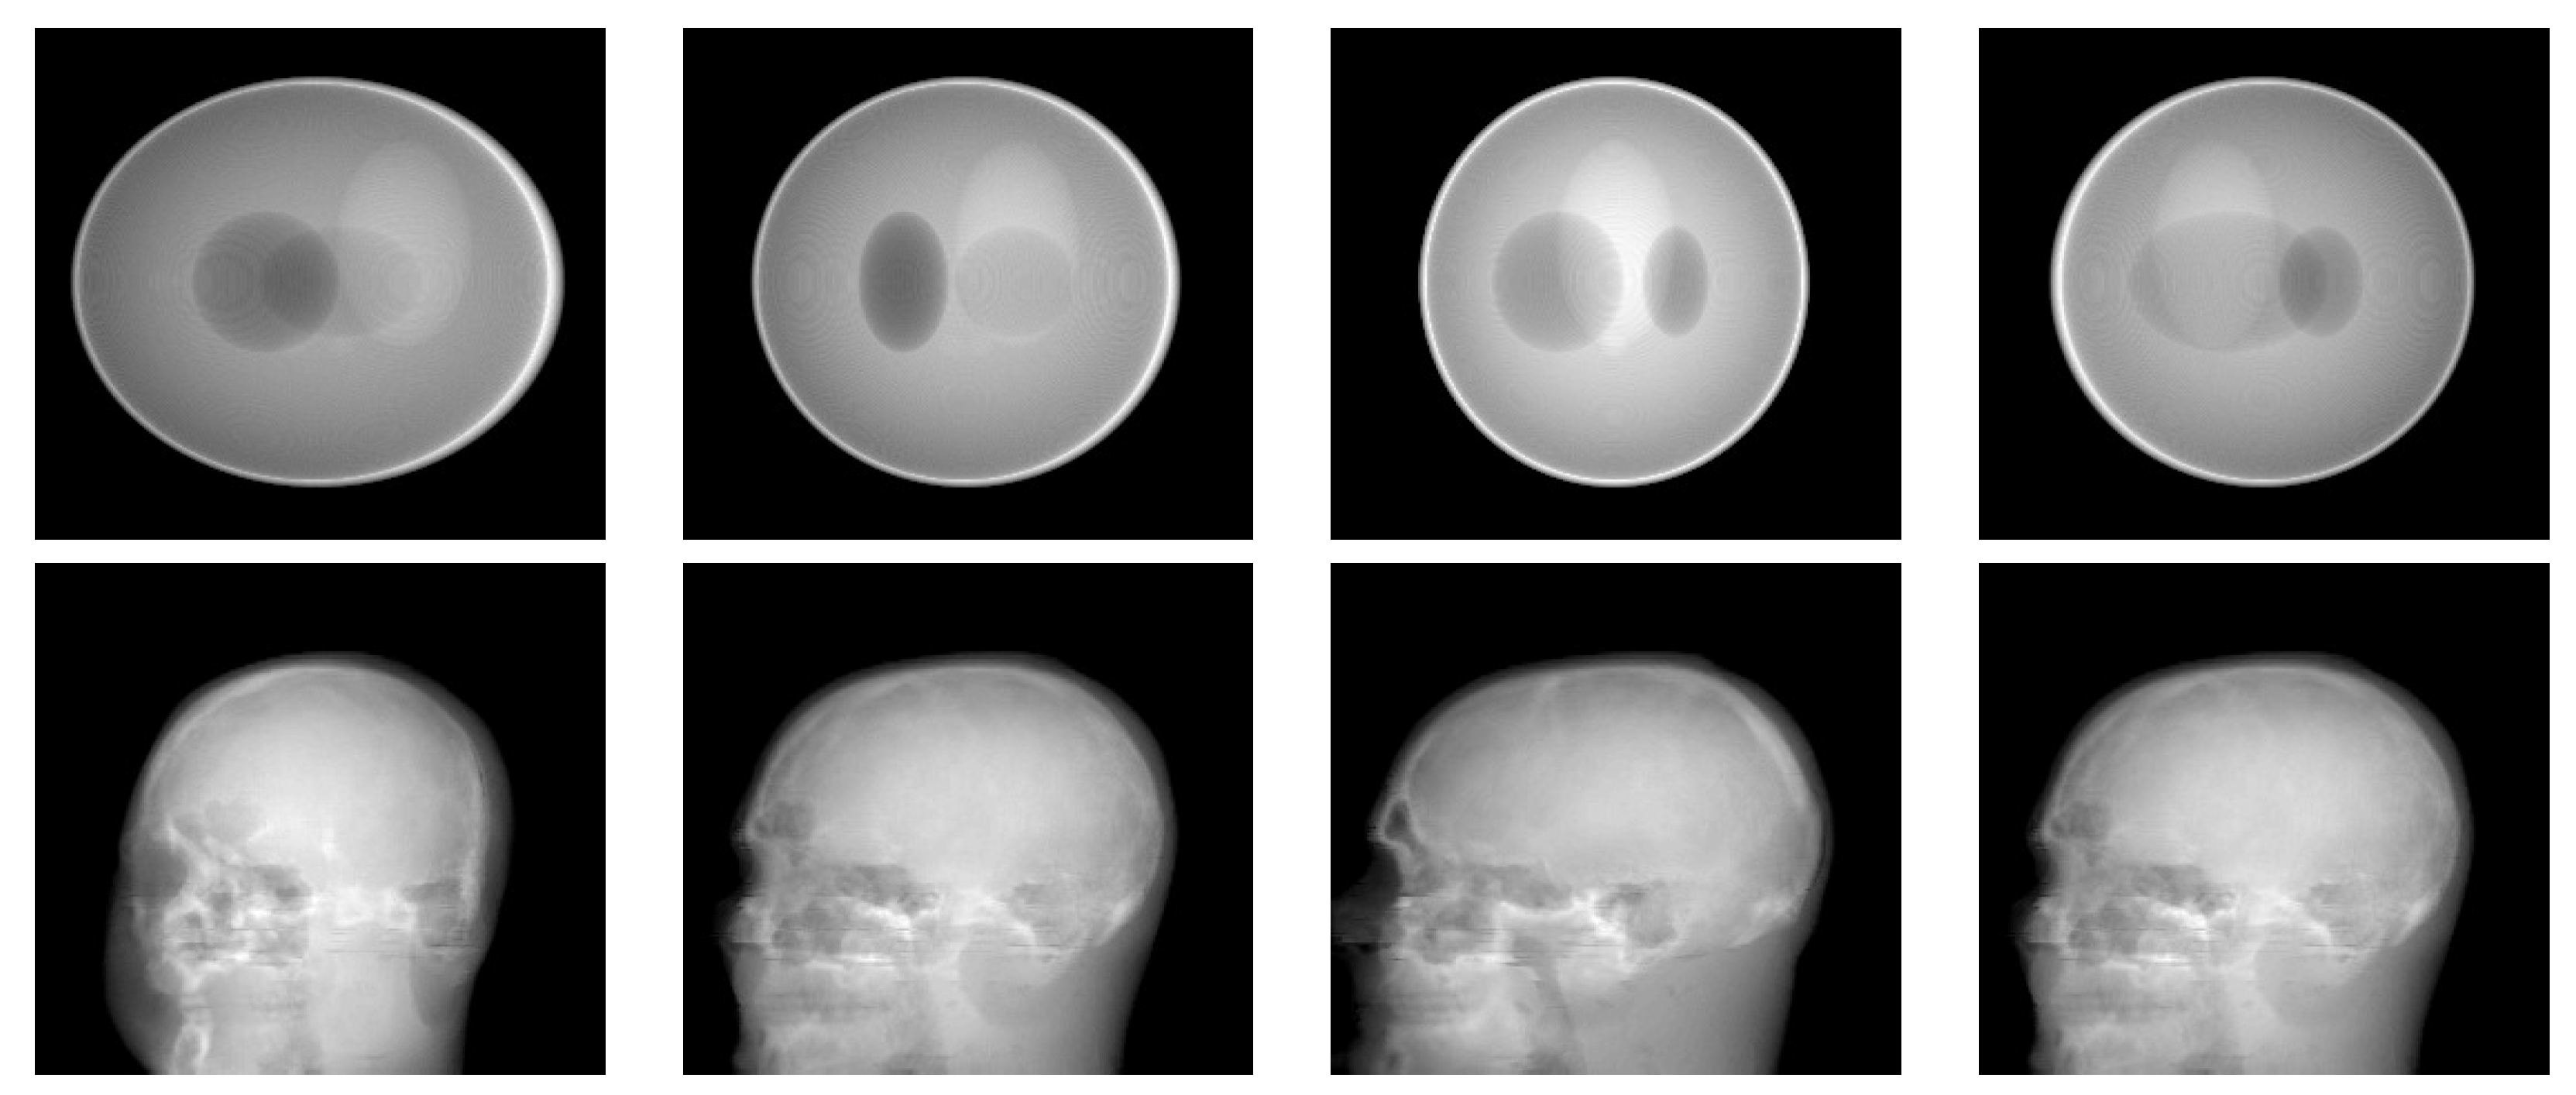

3.2. Simulation Results with a Limited Number of Projections

3.3. Simulation Results with a Limited Angle of Projections

| Shepp–Logan Phantom | ||||||||||||

| 180 Projections | 90 Projections | |||||||||||

| 40 dB | 20 dB | 40 dB | 20 dB | |||||||||

| QR | TV | HHBM | QR | TV | HHBM | QR | TV | HHBM | QR | TV | HHBM | |

| 60 Projections | 45 Projections | |||||||||||

| 36 Projections | 18 Projections | |||||||||||